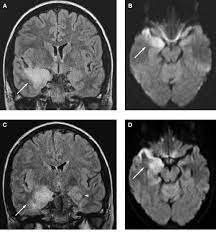

In children older than 3 months and in adults brain biopsy: Herpesviral encephalitis, or herpes simplex encephalitis (hse), is encephalitis due to herpes simplex virus. • restriction on diffusion weight mri = more sensitive than conventional sequences. Misra uk, hashmi aa, kalita j. Diagnostic uncertainty and empirical management in pcr negative encephalitis. It is a severe condition brain mri may show limbic encephalitis (55) or diffuse t2 and dwi hyperintensities in the white matter, associated with restricted diffusion (54). Herpes simplex encephalitis occurs as 2 distinct entities: Mri is the imaging of choice in suspected cases of viral encephalitis, although ct scanning may be used where mri facilities are not available. The patient had initially improved after medical treatment. Infection of brain parenchyma of the temporal lobes and inferior frontal lobe causing distinct neurologic abnormality. Dhawan a, kecskes z, jyoti r, kent al. Associated with hsv encephalitis (strong evidence). In addition, because of the involvement of the.

It is a severe condition brain mri may show limbic encephalitis (55) or diffuse t2 and dwi hyperintensities in the white matter, associated with restricted diffusion (54). Brain mri—increased t2 signal intensity in frontotemporal region → viral (hsv) encephalitis. Associated with hsv encephalitis (strong evidence). Provided cranial imaging has excluded any contraindications such as a space occupying lesion or severe cerebral oedema and brain shift, a csf. Having said that, mri with contrast is considered the most sensitive imaging modality, and findings are present in over half of individuals 8. In addition, because of the involvement of the. We performed volumetric measurements of the left and right temporal lobes and of cerebral oedema. Herpes simplex encephalitis occurs as 2 distinct entities: The study analysed serially acquired magnetic resonance images (mri), of patients with acute hsv encephalitis who had neuroimaging repeated within four weeks of the first scan. Pregnancy the most common cause of encephalitis in newborns is vaginal delivery from a mother who is infected with herpes simplex virus 2 (hsv 2). There is no particular age, sex, or seasonal predilection. Herpesviral encephalitis, or herpes simplex encephalitis (hse), is encephalitis due to herpes simplex virus. Severe infection, particularly untreated herpes simplex virus (hsv) encephalitis, can cause brain hemorrhagic necrosis.

Alpha coma in japanese encephalitis. Herpes simplex encephalitis occurs as 2 distinct entities: Brain mri—increased t2 signal intensity in frontotemporal region → viral (hsv) encephalitis. A case of granulomatous hsv encephalitis: Encephalitis caused by hsv type 1 is rare but can result in significant brain damage or death. Contrast enhancement is uncommon during the first week of the disease. The study analysed serially acquired magnetic resonance images (mri), of patients with. Its symptoms are fever, confusion, coma, and seizures. Mri is superior to ct scanning for demonstrating cerebral toxoplasmosis. Brain mri is shown in fig. Having said that, mri with contrast is considered the most sensitive imaging modality, and findings are present in over half of individuals 8. Associated with hsv encephalitis (strong evidence). There is no particular age, sex, or seasonal predilection.